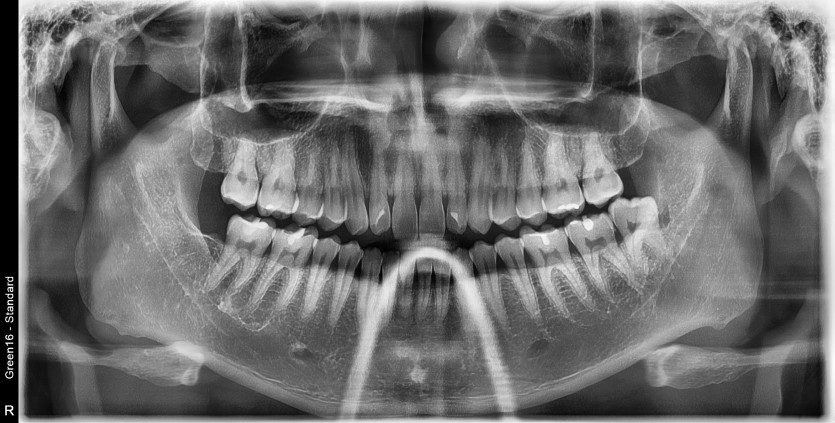

#38 사랑니 발치

구강 외과 전문의가 당일 발치했습니다.